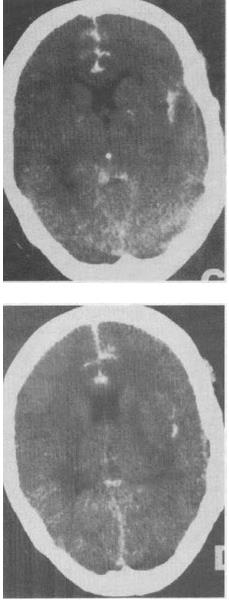

单项选择题 男性,55岁。被汽车撞倒半小时,昏迷状态。急诊平扫CT。检查图像如图所示,诊断最可能的是()。

A、脑实质出血

B、正常脑CT表现

C、硬膜下血肿

D、硬膜外血肿

E、蛛网膜下隙出血

• E